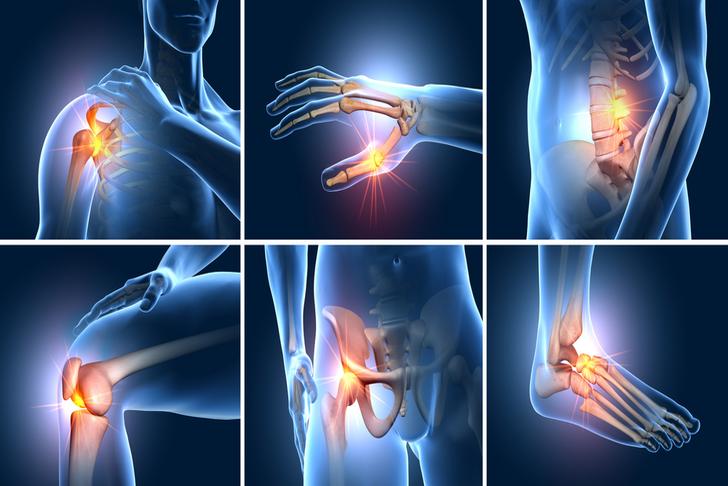

10 Symptoms of Osteoarthritis to Be Aware Of

Osteoarthritis, a degenerative joint disease, is the most common form of arthritis and affects millions of people worldwide. It occurs when the protective cartilage that cushions the ends of your bones wears down over time. In this article, we will discuss 10 common symptoms of osteoarthritis that you should be aware of.

Joint Pain

Joint pain is the most common symptom of osteoarthritis and typically worsens with activity and improves with rest[[1]]. Pain may be felt during or after movement and can range from mild to severe, depending on the extent of the disease.